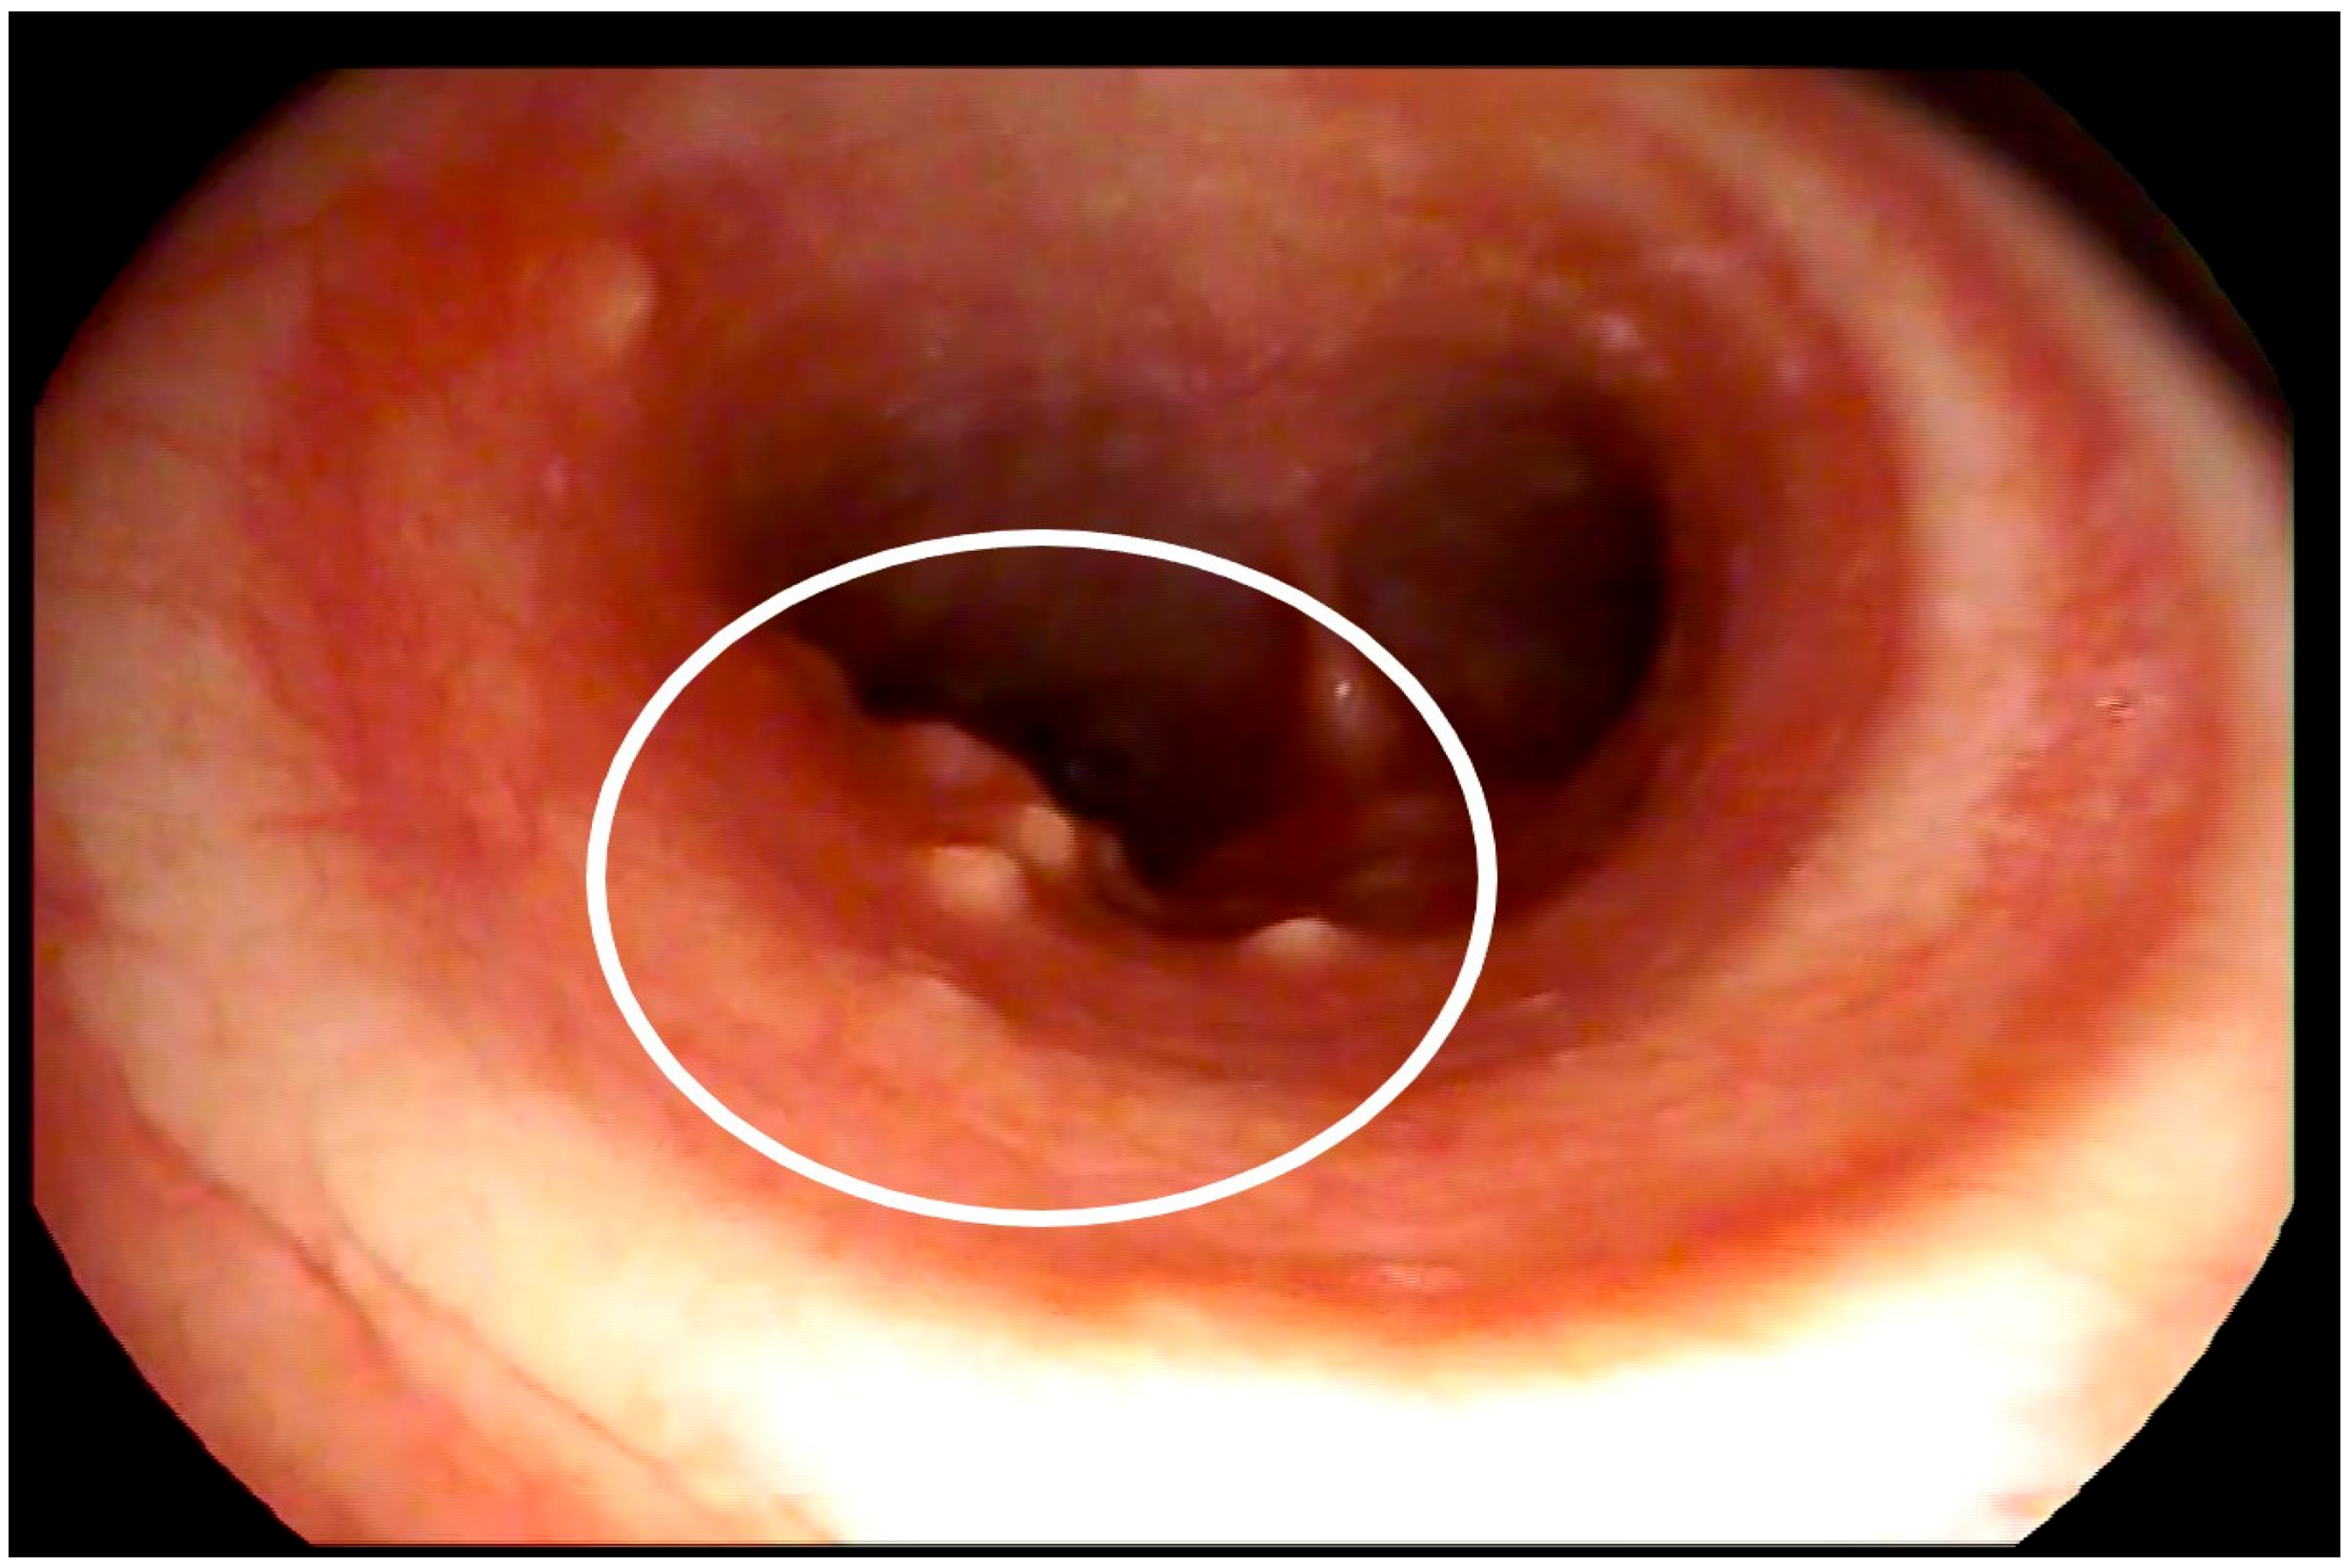

2. Case Report